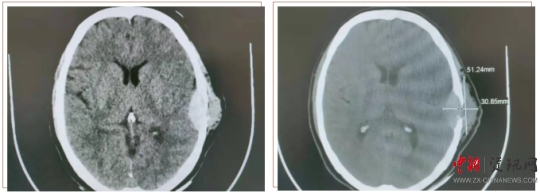

患者王某,女,58歲。半年前,患者用手觸摸頭部左耳上側(cè)時,發(fā)現(xiàn)一個小腫物,如花生米大小,當時沒太在意,十幾天前發(fā)覺腫物突然增大,由原來的1cm左右增大至5cm左右,且有壓痛感。于是來到上蔡縣人民醫(yī)院就診。神經(jīng)外科副主任楊學義接診后,安排患者做顱腦CT檢查,結(jié)果顯示:左側(cè)顳部占位侵犯腦膜及顱骨骨板,需要手術治療。遂收入神經(jīng)外科,經(jīng)過充分的術前討論,制定周密的手術方案后,由神經(jīng)外科主任周學良、副主任楊學義、主治醫(yī)師商文山、楊慶華歷時3個小時,成功將患者左側(cè)顳部5×4cm腫瘤完全切除,同時行“硬腦膜修補、顱骨修補手術”,術中精準解剖,精細操作,避免了血管及神經(jīng)等副損傷。術后顱腦CT掃描顯示:腫瘤完全切除,無腫瘤組織殘留;颊攥F(xiàn)已痊愈出院,未出現(xiàn)神經(jīng)功能障礙。目前正在隨訪中。

顱腦 CT 掃描顯示(下圖):左側(cè)顳部占位侵犯腦膜及顱骨骨板。